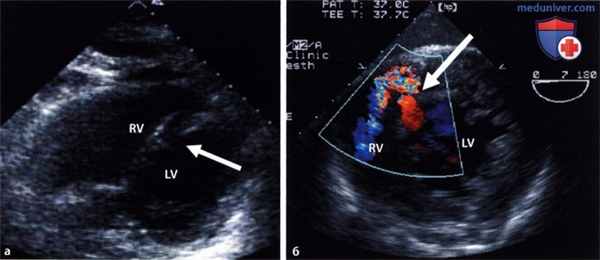

По данным трансторакальной эхокардиографии (ЭхоКГ) визуализировалось пролабирование передней створки митрального клапана в полость левого предсердия (рисунок 2).

Отмечалось незначительное увеличение полости левого предсердия в отсутствие увеличения полостей правого и левого желудочков, а также повышенная сократительная способность миокарда левого желудочка (ЛЖ) без признаков нарушения локальной сократимости миокарда, глобальная фракция выброса ЛЖ достигала 65% (рисунок 3).

Отмечались признаки умеренной легочной артериальной гипертонии, (систолическое давление в легочной артерии 47 мм.рт.ст.). Визуализация створок и подклапанных структур митрального клапана при трансторакальной ЭхоКГ была недостаточно информативной. В связи с этим потребовалось выполнение чреспищеводной ЭхоКГ, при которой была подтверждена выраженная митральная регургитация, обусловленная полным отрывом головки переднелатеральной папиллярной мышцы и пролабированием ее и передней створки митрального клапана в полость левого предсердия (рисунки 4 и 5).

| Рисунок 4. Чреспищеводная ЭхоКГ, 2-х камерная верхушечная позиция: пролабирование передней створки митрального клапана с папиллярной мышцей в полость левого предсердия | Рисунок 5. Чреспищеводная ЭхоКГ, 4-х камерная верхушечная позиция, цветовое допплеровское сканирование: не очень выраженная митральная регургитация |